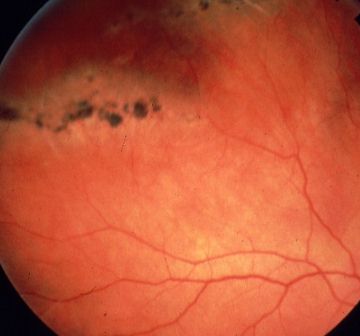

In chronic retinal detachment, the margin of the retina contains water marks with hyperp-igmentation. The surface may contain fibrous tissue. Look for retinodialysis which is a common cause of chronic inferior retinal detachment.

Watermarks in chronic retinal detachment